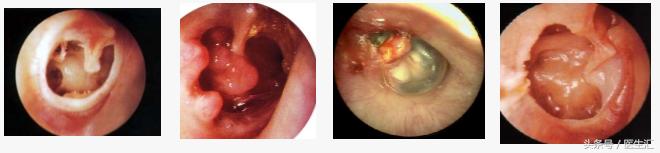

•左耳鼓膜紧张部后下边缘性穿孔,残余鼓膜大片钙化,鼓室内粘膜光滑。

•诊断:慢性化脓性中耳炎(左,后继胆)

•听力提高 •耳鸣消失